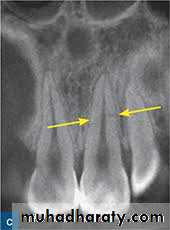

As the Periapical disease progress, resorption of the root can often be seen and extension in to the osseous support is depicted in a radiograph as loss of the bone pattern with rarefactionThe spread of infection depend on the anatomic relationships, resistance of the host, the no. and virulence of MO, resistance of MO.

F. Clinical evaluation1. Evaluation of radiographs - Periapical films at different angles and panoramic films to evaluate root length, location of adjacent roots, and location of major anatomical structures.

Occlusal films may also be useful, especially for palatal lesions.